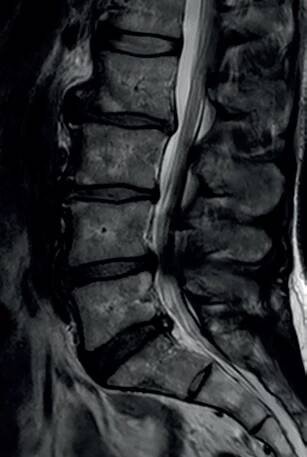

Lumbální spinální stenóza (LSS) je klinicko­-radiologický syndrom, nejnovější definice zohledňuje klinickou manifestaci i anatomické změny (zúžení páteřního kanálu). Převažujícím věkem začátku potíží je šestá dekáda. Onemocnění bývá poddiagnostikováno, přičemž přispívá k omezení mobility starších pacientů. Může se…

Lumbální spinální stenóza je onemocnění, při kterém dochází k postižení nervových vláken (nervových kořenů) vlivem zúžení páteřního kanálu v bederním úseku. Na tomto zúžení se podílí jednak vrozeně úzký páteřní kanál, jednak degenerativní…

Lumbální spinální stenóza (LSS) je definována jako nediskogenní komprese kaudy equiny způsobená spondylózními změnami, přičemž v některých případech se podílí i terén vrozeně úzkého páteřního kanálu.